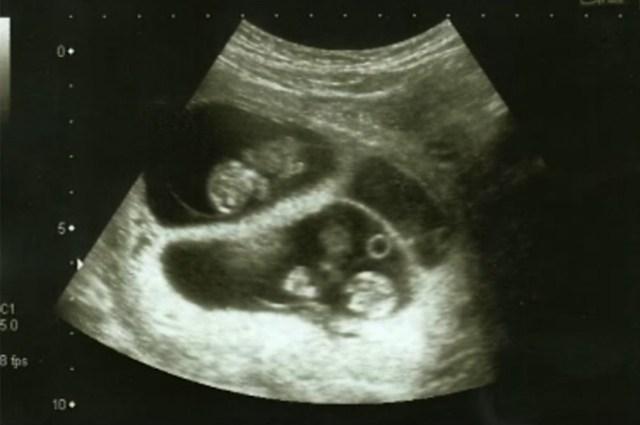

The eager mother knew she was pregnant, yet was totally stunned when her 21-week ultrasound uncovered somewhat more than one infant. Specialists informed her she was conveying not one, but rather four babies, which was essentially a scientific wonder, taking her age into account. Most young women would not even believe the screen if it happened to them.